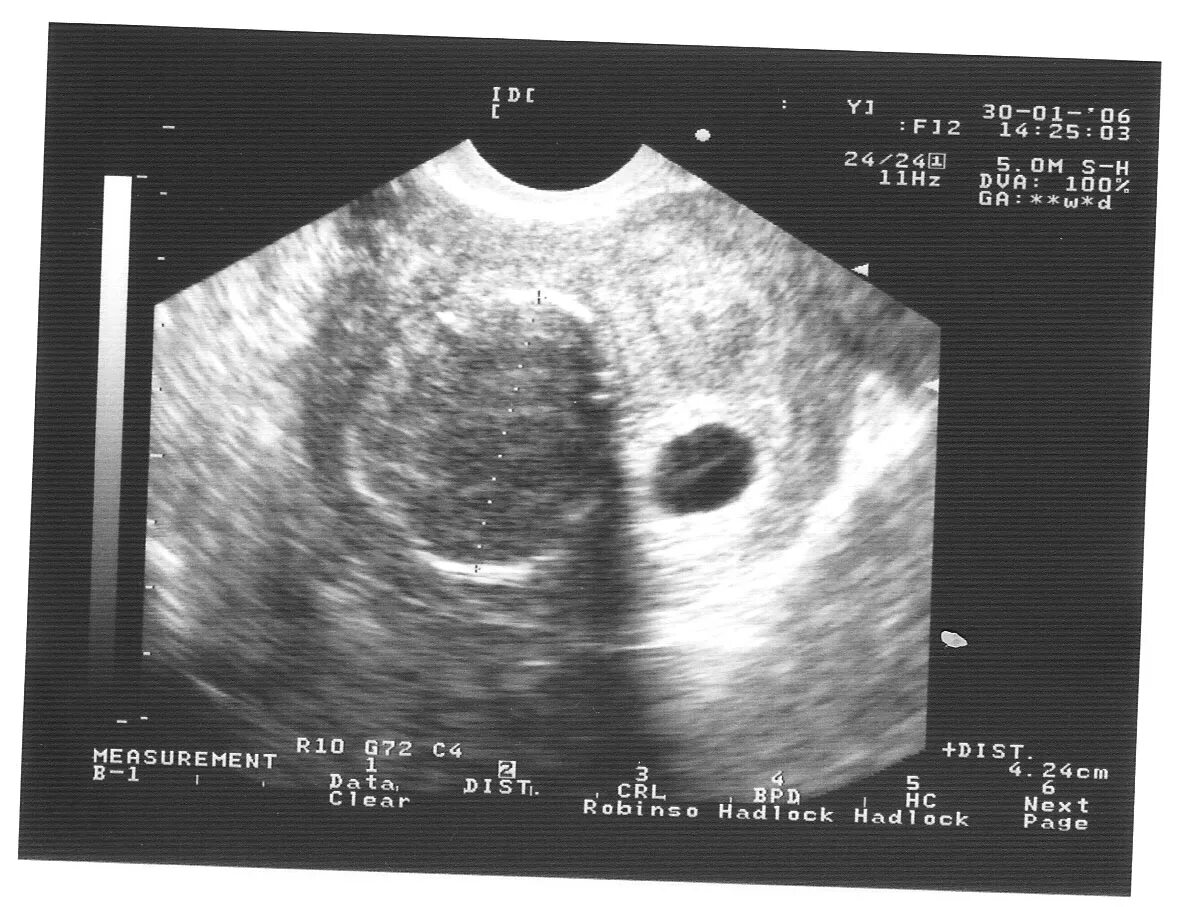

Узи при месячных